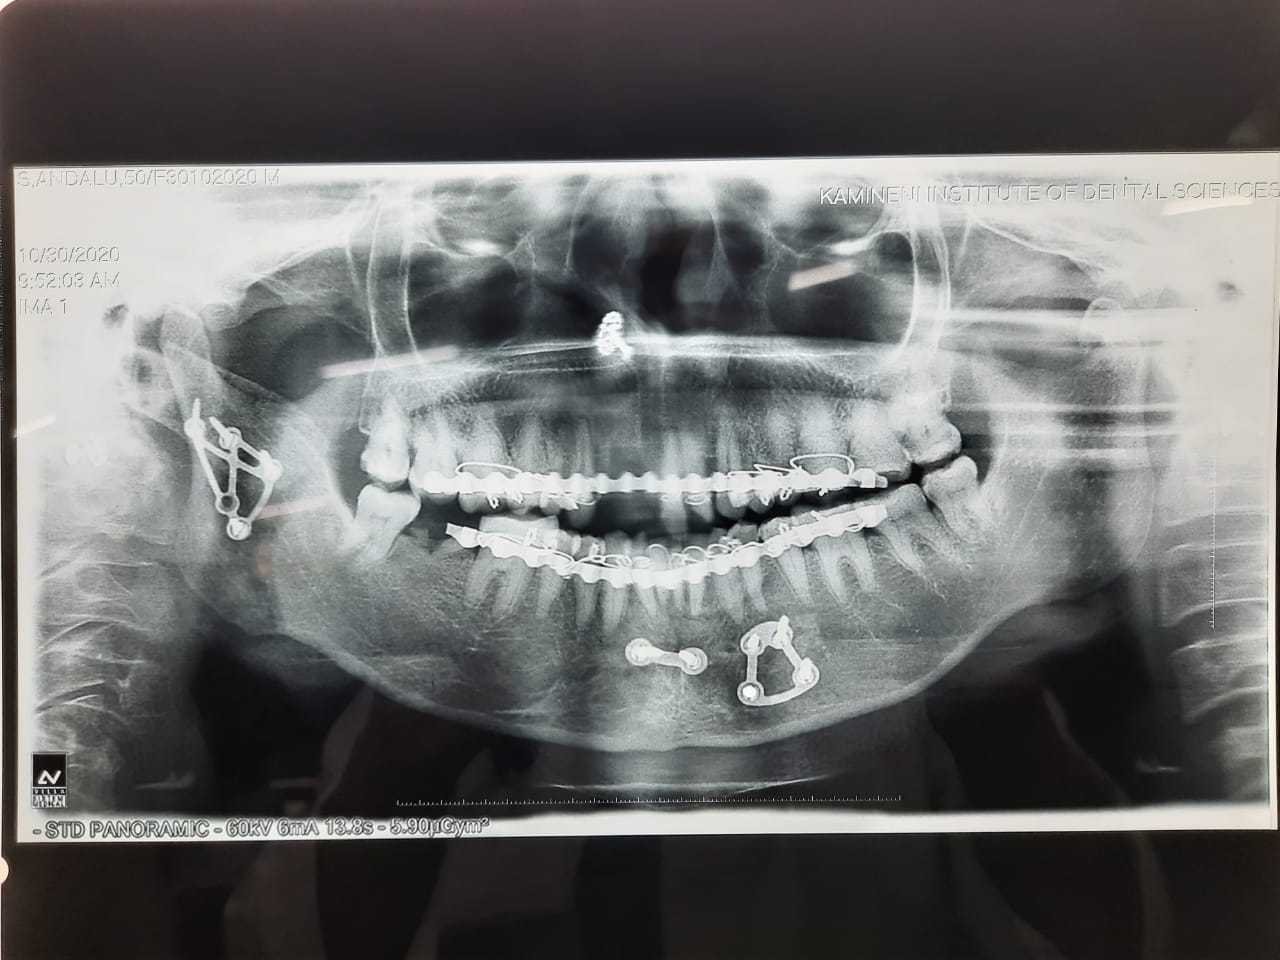

Fracture of the lower jaw condyle treated with open reduction and fixation. Post author:admin Post published:November 4, 2020 Post category:surgery Post comments:0 Comments You Might Also Like Happy Patients at Apollo DRDO Dental April 29, 2021 Leave a Reply Cancel replyCommentEnter your name or username to comment Enter your email address to comment Enter your website URL (optional) Save my name, email, and website in this browser for the next time I comment.